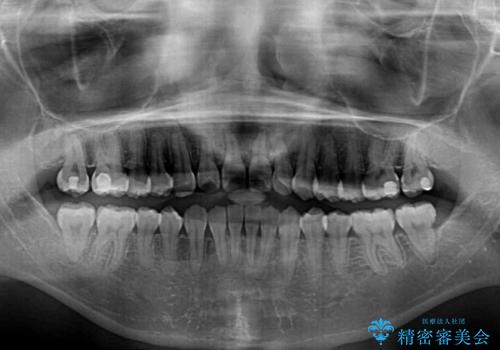

- 前歯の著しい叢生とクロスバイトを気にして来院された患者様です。

叢生が強いため、一見すると抜歯矯正と判断したくなりますが、下顎臼歯が舌側に倒れていることから、上顎骨を側方拡大し、非抜歯矯正の可能性を検討することとしました。

非抜歯矯正が可能となった場合には、インビザラインにて矯正治療を行うこととしました。

急速拡大装置による上顎骨の側方拡大が思った以上にうまくいき、非抜歯での矯正が可能となりました。

内側に倒れていた下顎の臼歯は起き上がり、清掃性も大幅に改善されました。